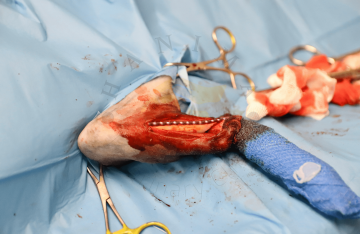

Trochleoplastika

Transpozice tuberositas tibiae

Náhrada předního zkříženého vazu

Amputace